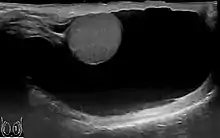

Through diagnostic ultrasound the accumulation of fluids can be diagnosed correctly.